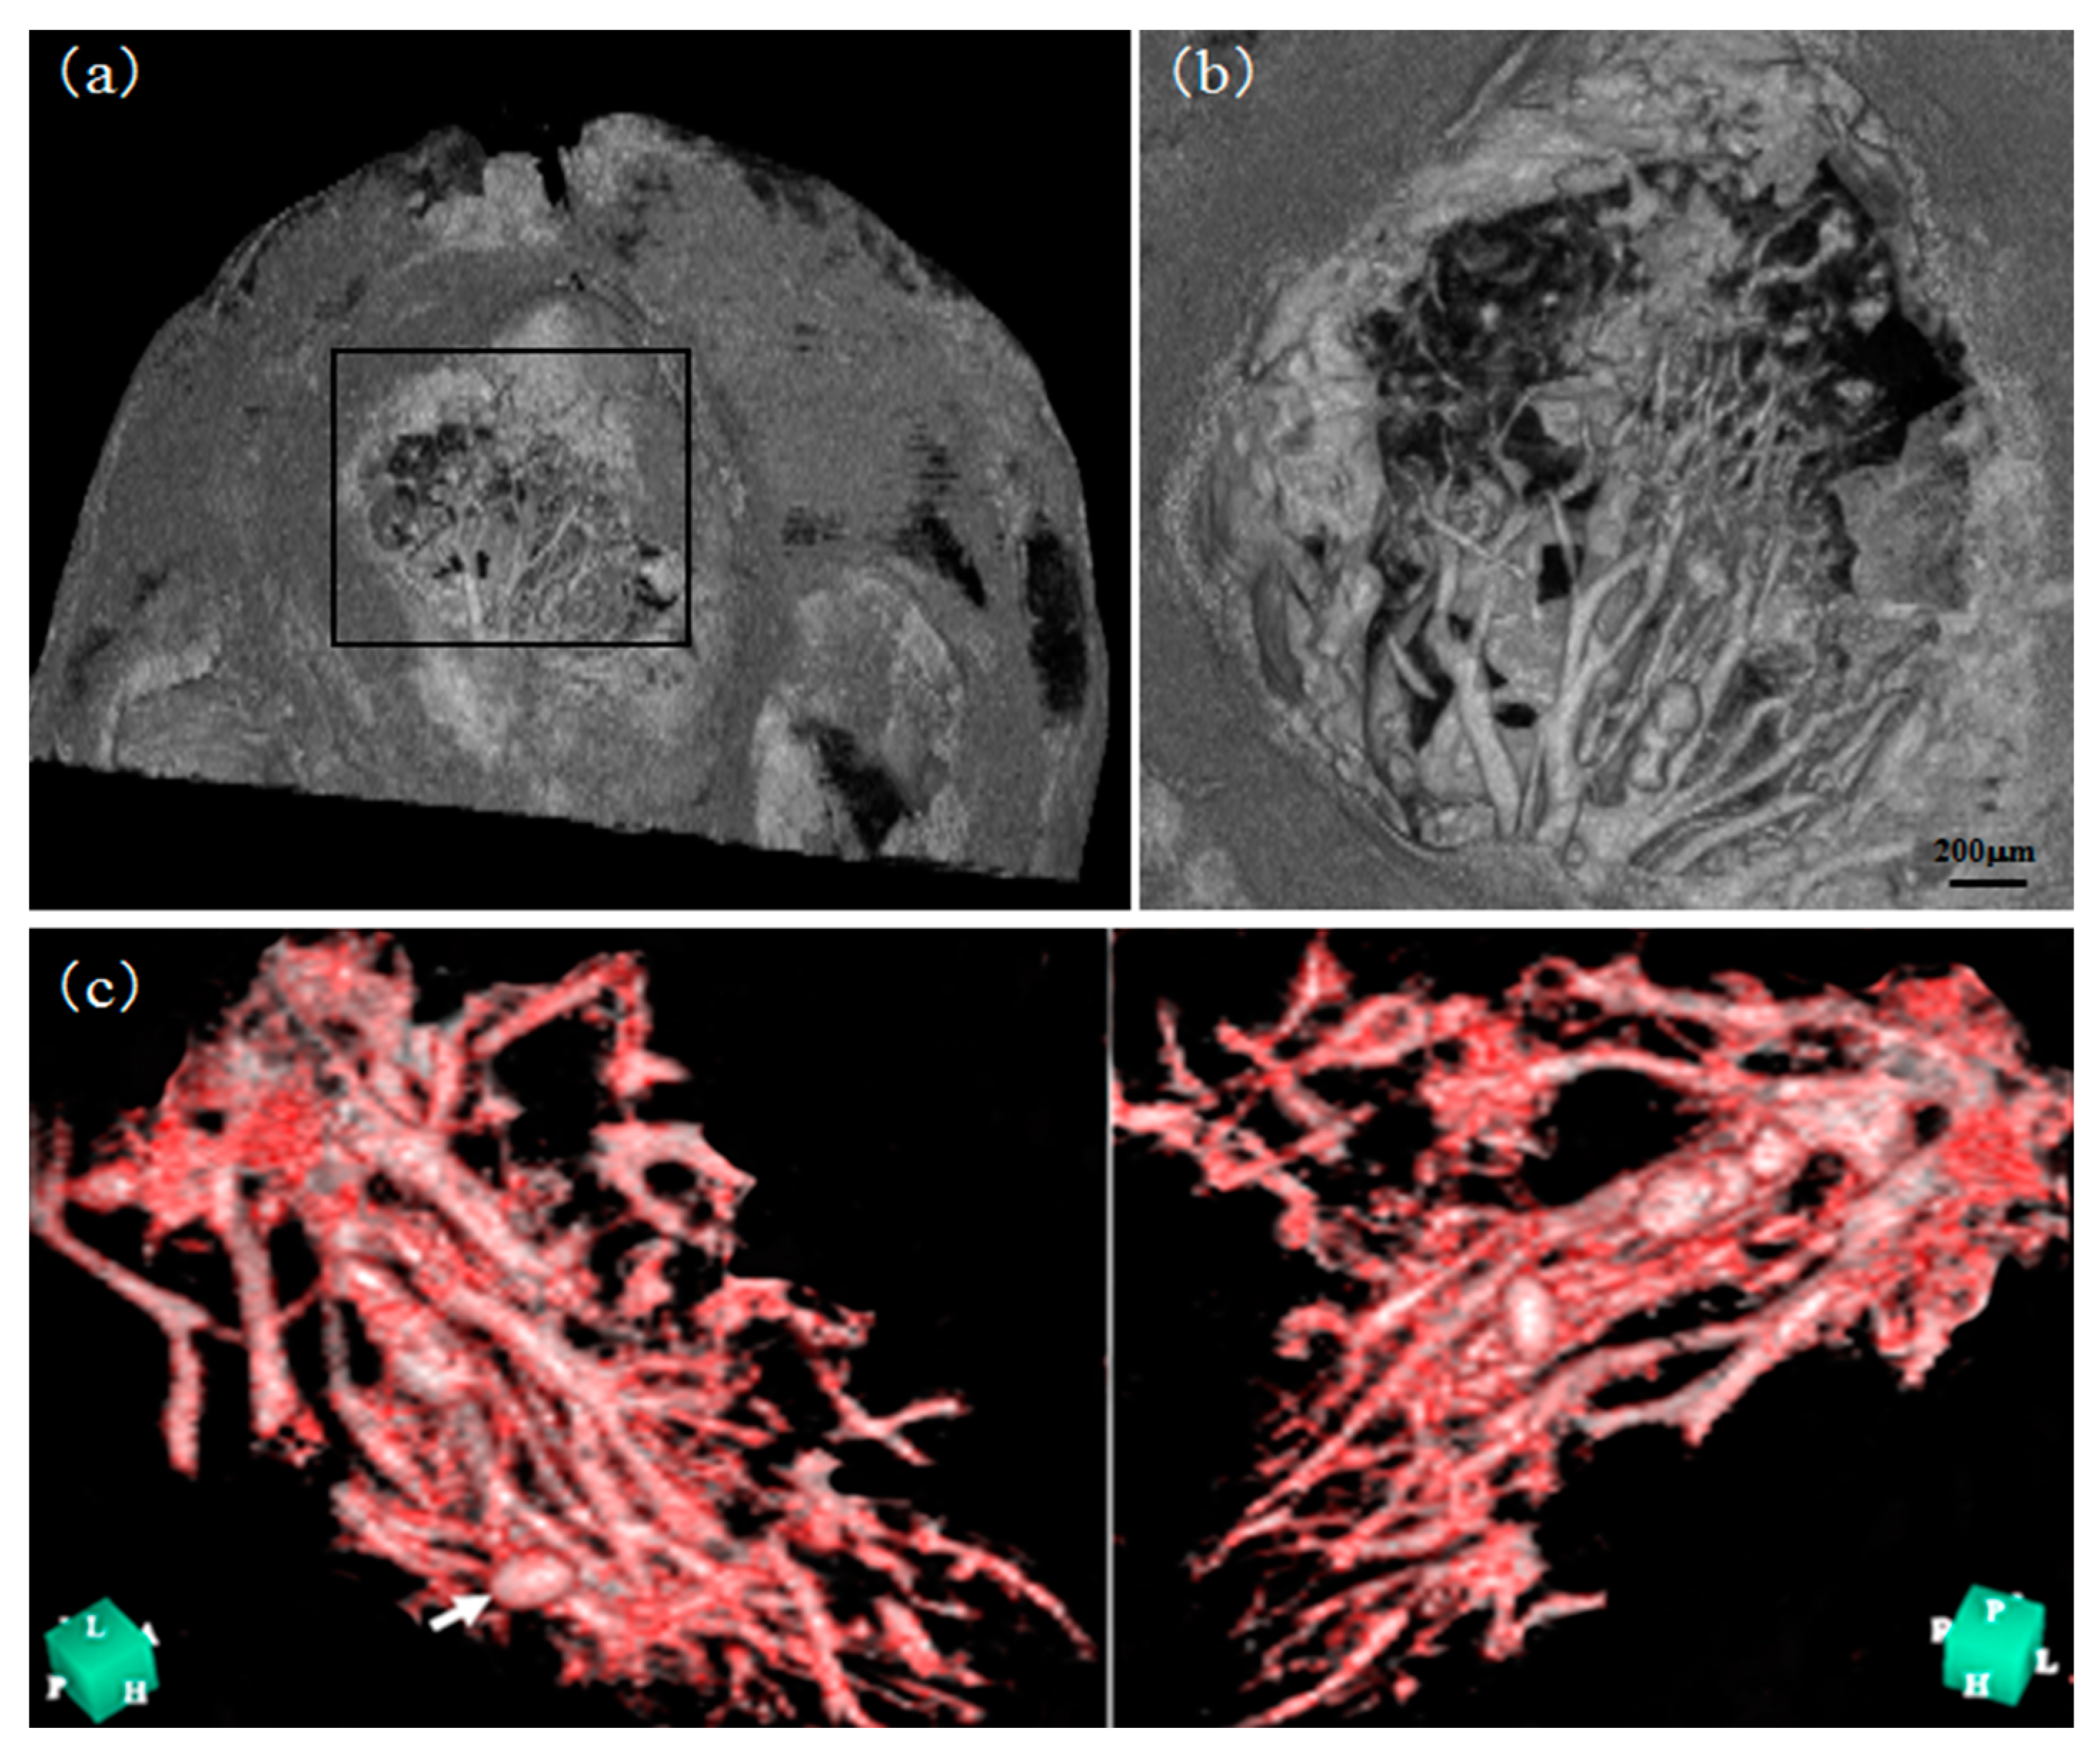

- Takeda, T.; Momose, A.; Wu, J.; Yu, Q.; Zeniya, T.; Lwin, T.-T.; Yoneyama, A.; Itai, Y. Vessel Imaging by Interferometric Phase-Contrast X-ray Technique. Circulation 2002, 105, 1708–1712. [Google Scholar] [CrossRef]

- Wu, J.; Takeda, T.; Lwin, T.T.; Momose, A.; Sunaguchi, N.; Fukami, T.; Yuasa, T.; Akatsuka, T. Imaging renal structures by X-ray phase-contrast microtomography. Kidney Int. 2009, 75, 945–951. [Google Scholar] [CrossRef] [Green Version]

- Esashi, S.; Yoneyama, A.; Thet-Thet-Lwin; Matsushima, T.; Maruyama, H.; Hyodo, K.; Takeda, T. Fine inner imaging of rat’s spleen by phase-contrast X-ray CT. Med. Imaging Technol. 2014, 32, 338–341. [Google Scholar] [CrossRef]